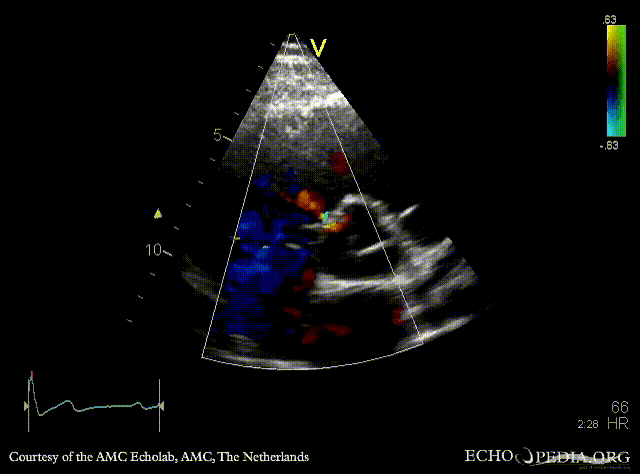

Perimembraneous VSD

E00685.gif

A5CH with Color Doppler